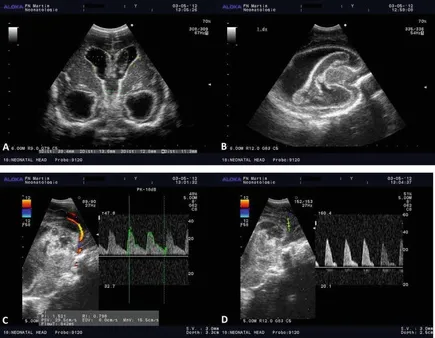

ಬೆಂಗಳೂರು: ಪ್ರತಿಷ್ಠಿತ ಮಲ್ಟಿ ಸ್ಪೆಷಾಲಿಟಿ ಆಸ್ಪತ್ರೆಯಾದ ಬನ್ನೇರುಘಟ್ಟ ರಸ್ತೆಯ ಅಪೋಲೋ ಆಸ್ಪತ್ರೆಯು, 1,000 ಟ್ರಾನ್ಸ್‌ ಕ್ರೇನಿಯಲ್ ಡಾಪ್ಲರ್ (ಟಿಸಿಡಿ) ಪ್ರಕ್ರಿಯೆಗಳನ್ನು ಯಶಸ್ವಿಯಾಗಿ ಪೂರ್ಣಗೊಳಿಸಿ ಮಹತ್ವದ ಸಾಧನೆ ಮಾಡಿದೆ. ಪಾರ್ಶ್ವವಾಯು ರೋಗನಿರ್ಣಯ ಮತ್ತು ನ್ಯೂರೋ ಕ್ರಿಟಿಕಲ್ ಕೇರ್ ಮೇಲ್ವಿಚಾರಣೆಯಲ್ಲಿ ಈ ತಂತ್ರಜ್ಞಾನವು ಅತ್ಯಂತ ಪರಿಣಾಮಕಾರಿಯಾಗಿದ್ದು, ಆಸ್ಪತ್ರೆಯ ಈ ಸಾಧನೆಯು ವೈದ್ಯಕೀಯ ಕ್ಷೇತ್ರದಲ್ಲಿ ಮಹತ್ವದ ಮೈಲಿಗಲ್ಲಾಗಿದೆ.

ಈ 1,000 ಪ್ರಕ್ರಿಯೆಗಳ ಅವಧಿಯಲ್ಲಿ, ಟಿಸಿಡಿ ತಂತ್ರಜ್ಞಾನವು ಆಸ್ಪತ್ರೆಯಲ್ಲಿ ಸಾಮಾನ್ಯ ಮತ್ತು ಸುಧಾರಿತ ಪಾರ್ಶ್ವವಾಯು ಮೌಲ್ಯಮಾಪನ ಮಾಡಲು ಅನುವು ಮಾಡಿಕೊಟ್ಟಿದೆ. ಇದರಲ್ಲಿ ತೀವ್ರ ಪಾರ್ಶ್ವವಾಯುವಿಗೆ ಒಳಗಾದ 350ಕ್ಕೂ ಹೆಚ್ಚು ರೋಗಿಗಳ ಮೇಲ್ವಿಚಾರಣೆಯನ್ನೂ ಮಾಡಲಾಗಿದೆ. ಈ ತಂತ್ರಜ್ಞಾನವು ಮೆದುಳಿನ ಒಳಗಿನ ರಕ್ತನಾಳಗಳ ಸಂಕುಚಿತಗೊಳ್ಳುವಿಕೆ, ಅಡೆತಡೆಗಳು ಮತ್ತು ರಕ್ತಪರಿಚಲನೆಯ ಅಸಮಾನತೆಯನ್ನು ತ್ವರಿತವಾಗಿ ಗುರುತಿಸಲು ಸಹಾಯ ಮಾಡಿದೆ.

ಇದು ವೈದ್ಯರಿಗೆ ಸಮಯೋಚಿತ ಚಿಕಿತ್ಸಾ ನಿರ್ಧಾರಗಳನ್ನು ತೆಗೆದುಕೊಳ್ಳಲು ಮತ್ತು ದ್ವಿತೀಯ ಪಾರ್ಶ್ವವಾಯು ತಡೆಗಟ್ಟುವಿಕೆಗೆ ಮಾರ್ಗದರ್ಶನ ನೀಡಲು ನೆರವಾಗಿದೆ. ಅಲ್ಲದೆ, ಇದು 'ಮೊಯ ಮೊಯಾ' ಕಾಯಿಲೆಯಲ್ಲಿ ಪರ್ಯಾಯ ರಕ್ತಪರಿಚಲನೆಯನ್ನು ಪತ್ತೆಹಚ್ಚಲು ಮತ್ತು ಸಬ್‌ ಕ್ಲೇವಿಯನ್ ಸ್ಟೀಲ್ ಫಿನಾಮಿನನ್ ನಂತಹ ನಾಳಗಳ ಪರಿಸ್ಥಿತಿಗಳ ಕುರಿತು ರೋಗನಿರ್ಣಯ ಮಾಡಲು ನೆರವು ನೀಡಿದೆ.

ಸಾಂಪ್ರದಾಯಿಕ ಇಮೇಜಿಂಗ್‌ ಗಿಂತ ಭಿನ್ನವಾಗಿ, ಇದು ಮೆದುಳಿನ ಧಮನಿಗಳ ಮೂಲಕ ರಕ್ತವು ನಿಜವಾಗಿ ಹೇಗೆ ಹರಿಯುತ್ತಿದೆ ಎಂಬ ಒಳನೋಟವನ್ನು ನೀಡುತ್ತದೆ. ಇದು ಪಾರ್ಶ್ವವಾಯು ಮೌಲ್ಯಮಾಪನ ಮತ್ತು ನ್ಯೂರೋಕ್ರಿಟಿಕಲ್ ಕೇರ್ ಮೇಲ್ವಿಚಾರಣೆಯಲ್ಲಿ ನಿರ್ಣಾಯಕ ಪಾತ್ರ ವಹಿಸುತ್ತದೆ. 1,000 ಪ್ರಕ್ರಿಯೆಗಳ ಈ ಮೈಲಿಗಲ್ಲನ್ನು ತಲುಪಿರುವುದು, ನಮ್ಮ ಸಮಗ್ರ ಪಾರ್ಶ್ವ ವಾಯು ಚಿಕಿತ್ಸೆಯಲ್ಲಿ ಈ ತಂತ್ರಜ್ಞಾನವು ಹೇಗೆ ಅತ್ಯಗತ್ಯ ಭಾಗವಾಗಿದೆ ಎಂಬುದನ್ನು ಸಾರುತ್ತದೆ ಮತ್ತು ರೋಗಿಗಳಿಗೆ ವೇಗವಾಗಿ ಹಾಗೂ ಹೆಚ್ಚು ನಿಖರವಾದ ಚಿಕಿತ್ಸಾ ನಿರ್ಧಾರಗಳನ್ನು ತೆಗೆದು ಕೊಳ್ಳಲು ನಮಗೆ ಸಹಾಯ ಮಾಡುತ್ತದೆ," ಎಂದು ತಿಳಿಸಿದರು.

ಬನ್ನೇರುಘಟ್ಟದ ಅಪೋಲೋ ಆಸ್ಪತ್ರೆಯ ಕನ್ಸಲ್ಟೆಂಟ್ ನ್ಯೂರಾಲಜಿಸ್ಟ್ ಡಾ. ಗುರುಚರಣ್ ಅಡೂರ್ ಅವರು ಮಾತನಾಡಿ, "ಪಾರ್ಶ್ವವಾಯು ರೋಗನಿರ್ಣಯದ ಹೊರತಾಗಿ, ಟಿಸಿಡಿ ಹಲವಾರು ಸಂಕೀರ್ಣ ನರವೈಜ್ಞಾನಿಕ ಸಮಸ್ಯೆ ಪರಿಹಾರದ ಸಂಬರ್ಭದಲ್ಲಿ ಬಹಳ ಉಪಯುಕ್ತ ವೆಂದು ಸಾಬೀತಾಗಿದೆ. ಸಬರಾಕ್ನಾಯಿಡ್ ಹೆಮರೇಜ್ ಮತ್ತು ಟ್ಯೂಬರ್ಕುಲರ್ ಮೆನಿಂಜೈಟಿಸ್ ರೋಗಿಗಳಲ್ಲಿ ಮೆದುಳಿನ ರಕ್ತನಾಳಗಳ ಸಂಕುಚಿತಗೊಳ್ಳುವಿಕೆಯನ್ನು ಮೇಲ್ವಿಚಾರಣೆ ಮಾಡಲು ಇದು ನಮಗೆ ಸಹಾಯ ಮಾಡಿದೆ. ಸಾಂಪ್ರದಾಯಿಕ ಪರೀಕ್ಷೆಗಳಲ್ಲಿ ಪತ್ತೆಯಾಗದ ಸಮಸ್ಯೆಗಳನ್ನು ಗುರುತಿಸಲು ಸಹ ಇದು ನೆರವಾಗಿದೆ. 'ಬಬಲ್ ಟಿಸಿಡಿ' ಬಳಸುವ ಮೂಲಕ, ನಾವು 'ಪೇಟೆಂಟ್ ಫೋರಾಮೆನ್ ಓವೇಲ್' (ಹೃದಯದ ರಂಧ್ರದ ಸಮಸ್ಯೆ) ಹೊಂದಿರುವ 32 ರೋಗಿಗಳನ್ನು ಗುರುತಿಸಿದ್ದೇವೆ, ಇವರಲ್ಲಿ ಅನೇಕರಿಗೆ ಈ ಹಿಂದೆ ಎಕೋಕಾರ್ಡಿಯೋಗ್ರಫಿಯಲ್ಲಿ ಈ ಸಮಸ್ಯೆ ಪತ್ತೆಯಾಗಿರಲಿಲ್ಲ" ಎಂದು ಮಾಹಿತಿ ನೀಡಿದರು.

ರೋಗನಿರ್ಣಯಕ್ಕೆ ನೆರವಾಗುವ ಜೊತೆಗೆ, ಟಿಸಿಡಿ ತಂತ್ರಜ್ಞಾನವು 30 'ಬ್ರೈನ್ ಡೆತ್' (ಮೆದುಳು ನಿಷ್ಕ್ರಿಯ) ಮೌಲ್ಯಮಾಪನ ಮಾಡಲು ನೆರವು ನೀಡಿದೆ. ಸಮಯದ ಮಿತಿ ಇರುವ ಇಂತಹ ಕ್ಲಿನಿಕಲ್ ಸಂದರ್ಭಗಳಲ್ಲಿ, ಮೆದುಳಿನ ರಕ್ತಪರಿಚಲನೆ ಸ್ಥಗಿತಗೊಂಡಿರುವ ವಿಶಿಷ್ಟ ಮಾದರಿ ಗಳನ್ನು ಪತ್ತೆ ಹಚ್ಚುವ ಮೂಲಕ ಇದು ದೃಢೀಕೃತ ಪುರಾವೆಗಳನ್ನು ಒದಗಿಸಿದೆ. ಹಾಸಿಗೆಯ ಪಕ್ಕದಲ್ಲೇ ಪುನರಾವರ್ತಿಸಬಹುದಾದ ವಿಧಾನವಾಗಿರುವುದರಿಂದ, ಇದು ಉತ್ತಮ ಕ್ಲಿನಿಕಲ್ ನಿರ್ಧಾರಗಳನ್ನು ತೆಗೆದುಕೊಳ್ಳಲು ಮತ್ತು ಅಂಗಾಂಗ ದಾನದ ಪ್ರಕ್ರಿಯೆಗಳನ್ನು ಸುಗಮಗೊಳಿಸಲು ಸಹಾಯ ಮಾಡಿದೆ.